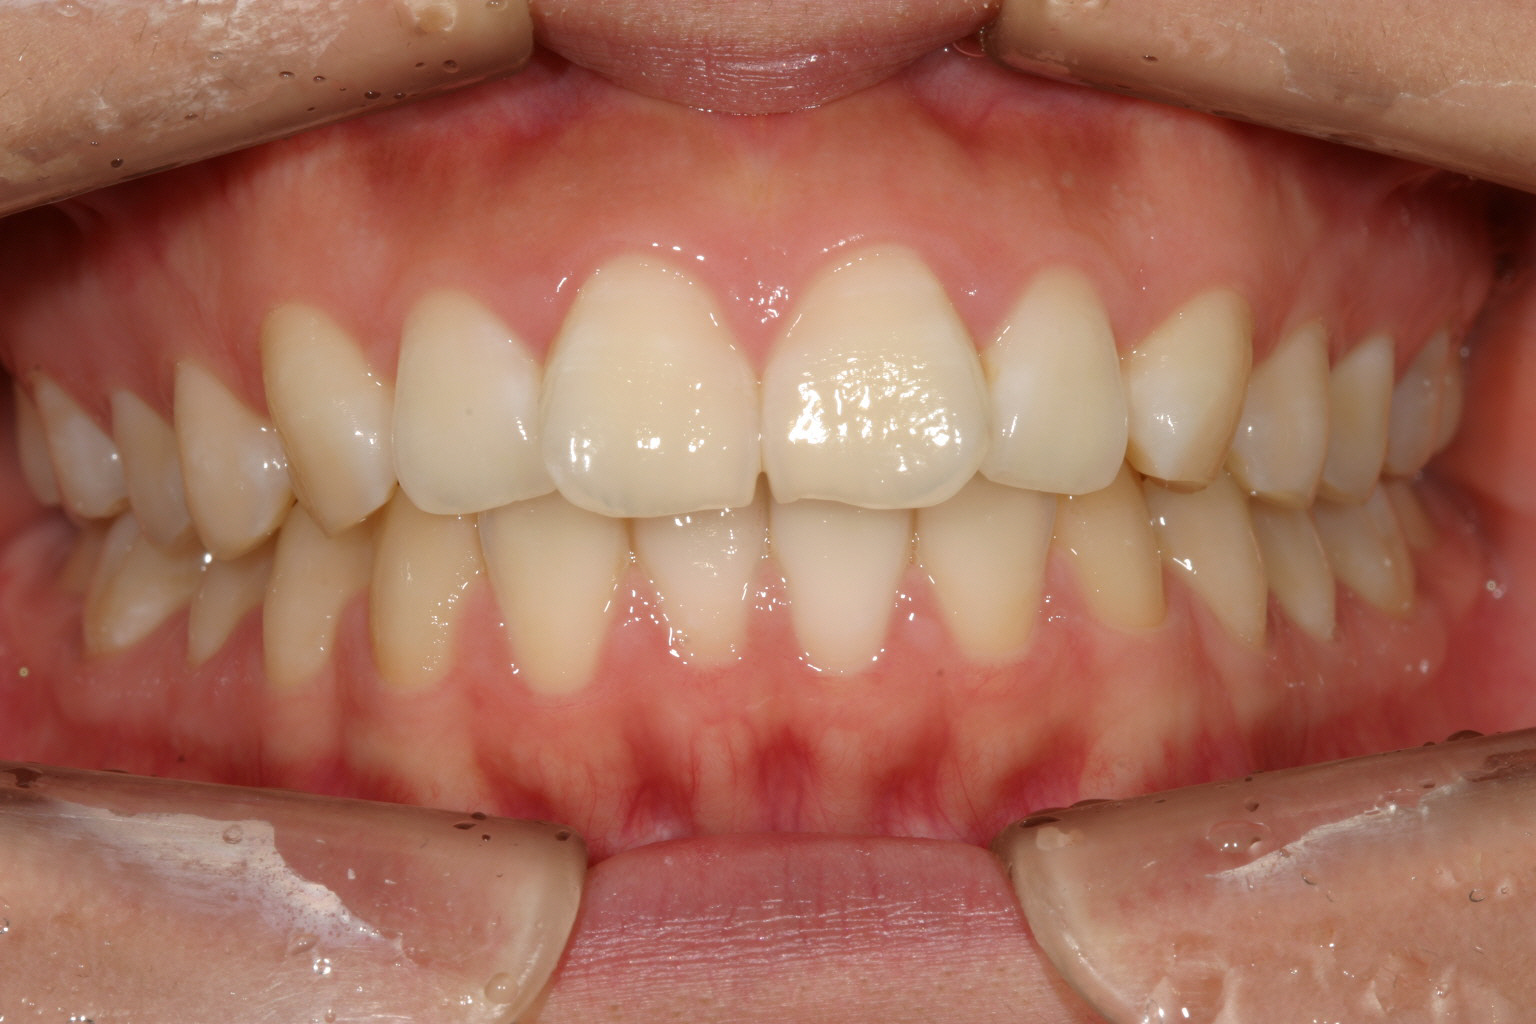

前歯がすこしねじれてる。

前歯が翼状捻転してます。

翼状捻転してる分少し出てます。